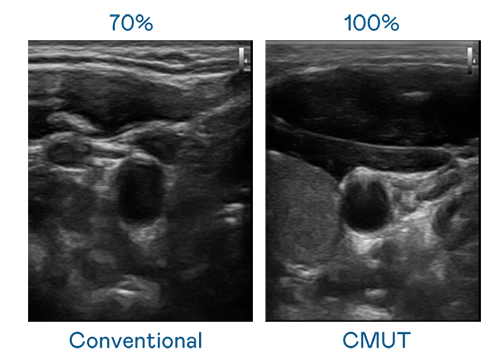

CMUT 技术是一种用电容式微机电元件来产生超音波讯号的技术。与传统 PZT 压电式技术相比,CMUT 频宽增加 30%,更宽频的超音波讯号让影像解析度大幅提升,是实现高影像品质医疗超音波扫描、促进精准医疗发展的关键技术。

超音波影像的解析度高低,首先取决于探头能发出的讯号频宽。彩虹多多 CMUT 可提供高清晰的超音波讯号,提供高频宽、高灵敏度、影像纹理细节更高的超音波影像,协助医护人员缩短影像判读时间及利用精准的医疗影像进行诊断。